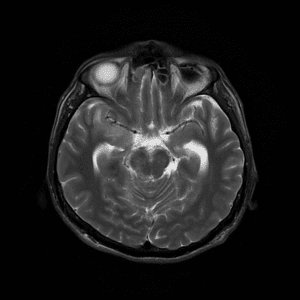

Cavernoma

Lượt xem: 237» 19-06-2020 -